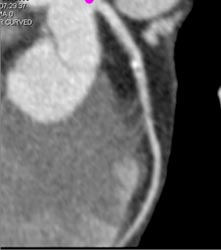

Diseased Bypass Graft